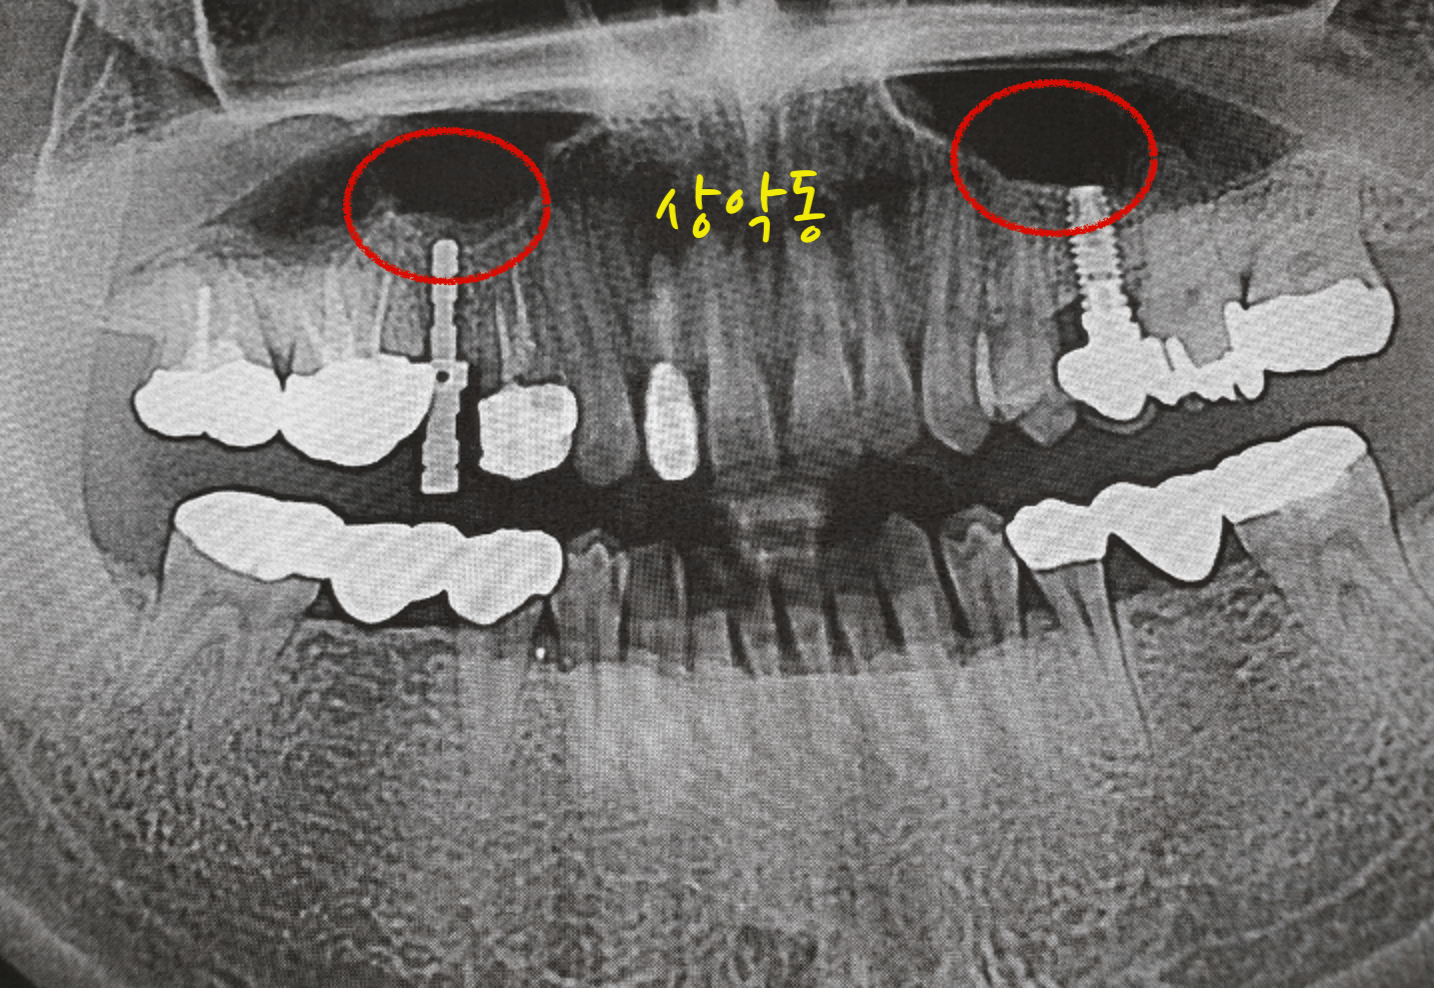

치아가 좋지 않다보니 임플란트를 심으면서 상악동 거상술을 두번 하게 되었습니다. 상악동은 아랫어금니 쪽이 아닌 윗어금니 쪽에서 코와 이빨사이에 빈공간을 이야기 합니다. 지금부터 상악동 거상술 비용 및 보험 청구 후기 경험을 공유 합니다.

상악동 거상술

상악동 거상술은 윗쪽 어금니와 코사이에 존재하는 부비동 공간에 그막을 살작들어서 파열되지 않게 임플란트를 삽입하기 위해 하는 시술입니다.